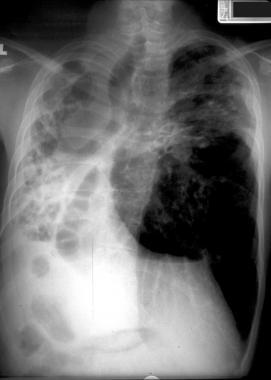

【一文总结囊性纤维化的肺部影像学特征|相“影”成趣】患有轻度肺部疾病的囊性纤维化患者的胸片可能正常 。 由于黏液堵塞而导致的肺部过度充气可能是儿童或成人时期的唯一表现 。

中度或晚期时的肺部可能出现线状阴影和散在结节 , 并可能观察到节段性、斑片性或小叶性肺不张 , 儿童比成人更为多见 , 通常表现在右上叶 。

图1 患囊性纤维化的青年男性 , 显示过度充气和上叶支气管扩张 。